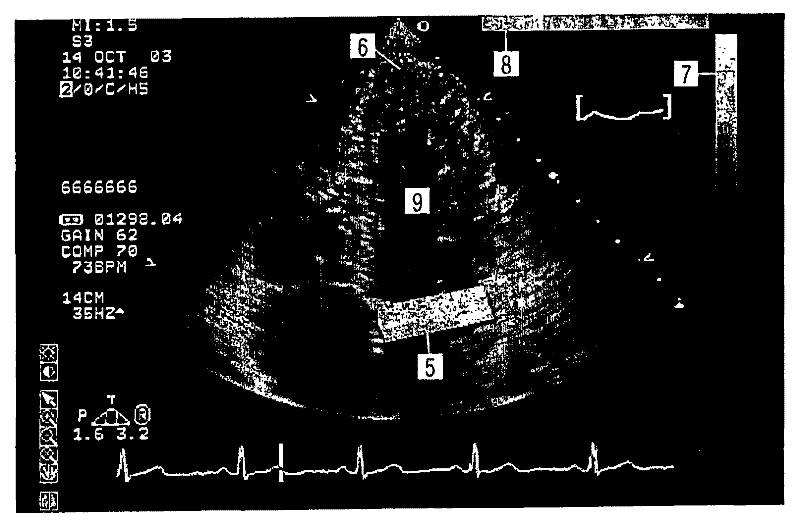

缺血性心脏病的超声诊断

CN101001574A

皇家飞利浦电子股份有限公司

I·萨尔戈 | A·达文波特 | W·克尔顿